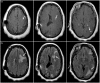

The use of flow diverting stents for wide based, intracranial aneurysms has become an invaluable treatment option. While intracranial hemorrhage and ischemic stroke from dislodged atherosclerotic emboli are common adverse events, the potential for delayed granulomatous inflammation from possible hydrophilic polymer emboli is rarely recognized. We present a unique case in which visible chipping of the pusher wire for stent placement was observed, followed by clinical and radiographic evidence suggestive of a delayed foreign body reaction to intracranial hydrophilic polymer emboli. A 55-year-old woman underwent placement of a Pipeline embolization device for a left-sided, broad-based aneurysm at the base of the internal carotid artery and posterior communicating artery. Two months later she developed right-sided focal neurological deficits. Imaging showed ipsilateral focal edema and enhancing lesions with contrast. Although not confirmed with biopsy and histopathology, clinical and radiographic evidence suggests that this patient probably experienced a delayed foreign body reaction to hydrophilic polymer emboli from compromised procedural equipment during flow diverting stent placement. Although previously described, this is the first instance to our knowledge in whichvisible chipping of the pusher wire was observed on a Pipeline embolization device.